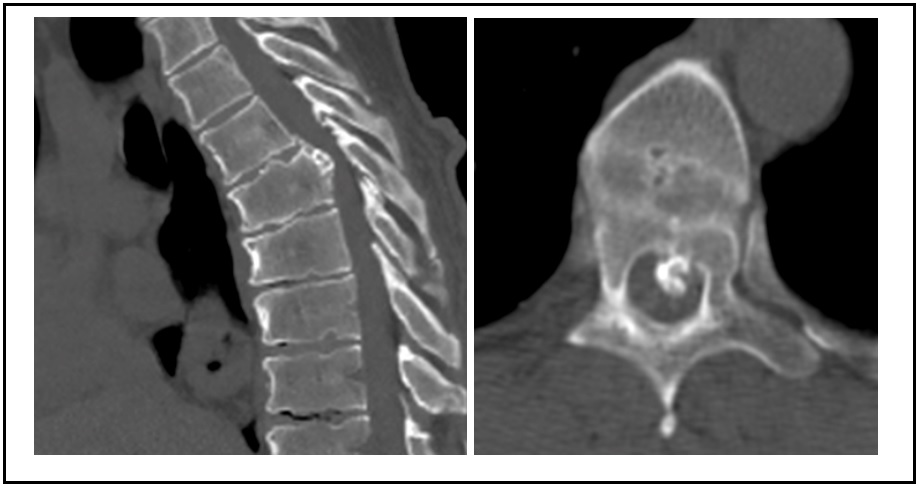

We present the case of a 64-year-old male with spinal compression symptoms, central disc herniation calcified at the fifth thoracic vertebra, which migrated to the lower end of the sixth thoracic vertebra. Diagnosis was clear for spinal cord compression. Partial posterior corpectomy of the sixth vertebra was performed with a minimally invasive transthoracic transpleural lateral approach and without additional fixation. The patient had a good outcome on follow-up, without progression of neurological symptoms or residual rib pain.